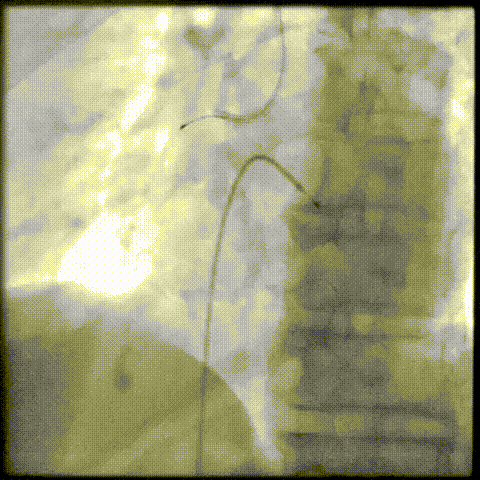

PCI过程-再次冲击波球囊PTCA

沿导丝送3.5×12mmGennWave冲击波球囊至RCA严重钙化病变处,充盈1:1比例造影剂盐水,以4atm低压扩张,每周期给予10秒、每秒1次血管内冲击波治疗后扩张至6atm,共进行8周期血管内冲击波治疗。

PCI过程-球囊PTCA

冲击波球囊完成后,进一步预处理,再反复应用切割球囊 3.0X10mm、非顺应性球囊 3.5X15mm等球囊反复由远及近进行扩张。